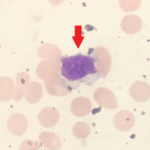

Findings/Diagnosis